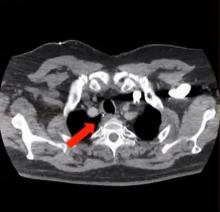

This videos shows a successful VATS resection of an ectopic parathyroid adenoma, which was deemed unresectable via standard approaches.